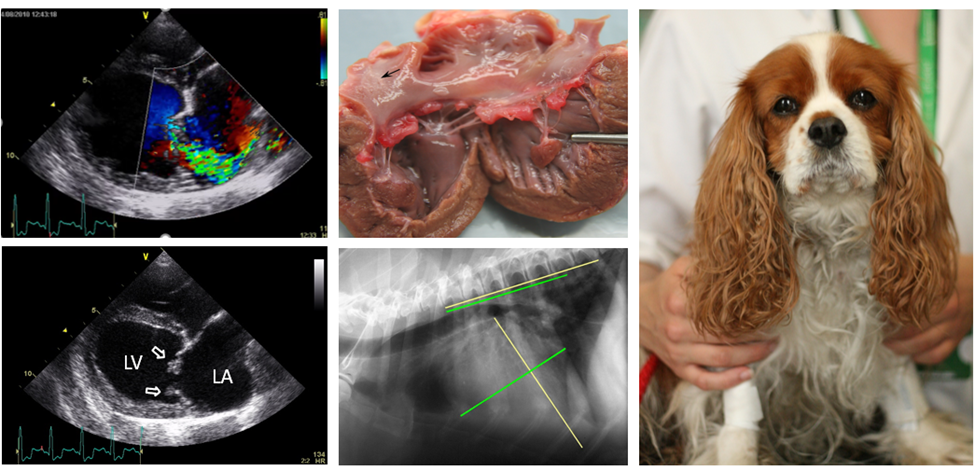

Congestive Heart Failure Symptoms In Dogs

Left Sided Congestive Heart Failure Clinician s Brief